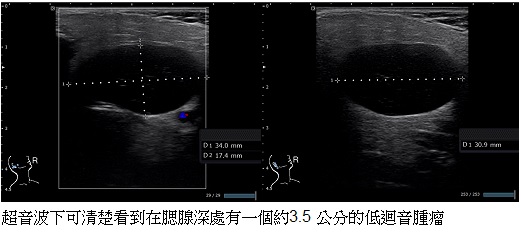

35歲呂小姐,覺得自己左右臉有點不對稱大約半年,最近一個月發現似乎右邊的耳下的臉部特別腫大,因此先前往醫院就診安排電腦斷層,發現右側的腮腺看起來較左邊腫大,卻沒有看到明顯的腫塊,後來偶然在網路上查到我們診所有頭頸部超音波檢查,因此特地找時間到我們診所接受檢查,在理學檢查下發現,的確呂小姐的右側耳下處雖然沒有明顯摸到邊緣明顯的腫瘤,但是確實有腫大的現象,在超音波底下,就可以清楚的看到在腮腺的深處有一顆腫瘤,經過了超音波引導細針穿刺,確認了這個腫瘤是良性的Warthin氏瘤。終於在釐清臉不對稱的真正原因後,呂小姐接受手術,根除了這個困擾了她半年的問題。

以呂小姐的例子來說,她的腮腺腫瘤位於深部,因此在觸診時,只能感覺到腮腺的位置左右不對稱,無法清楚的摸出有腫塊,偏偏做了電腦斷層,也沒有明確的顯影出腫塊,因此在一開始的診斷上,確實讓醫師吃足了苦頭,所幸後來在頭頸部超音波這項利器的協助下,終於揪出了在深層的腮腺腫瘤。